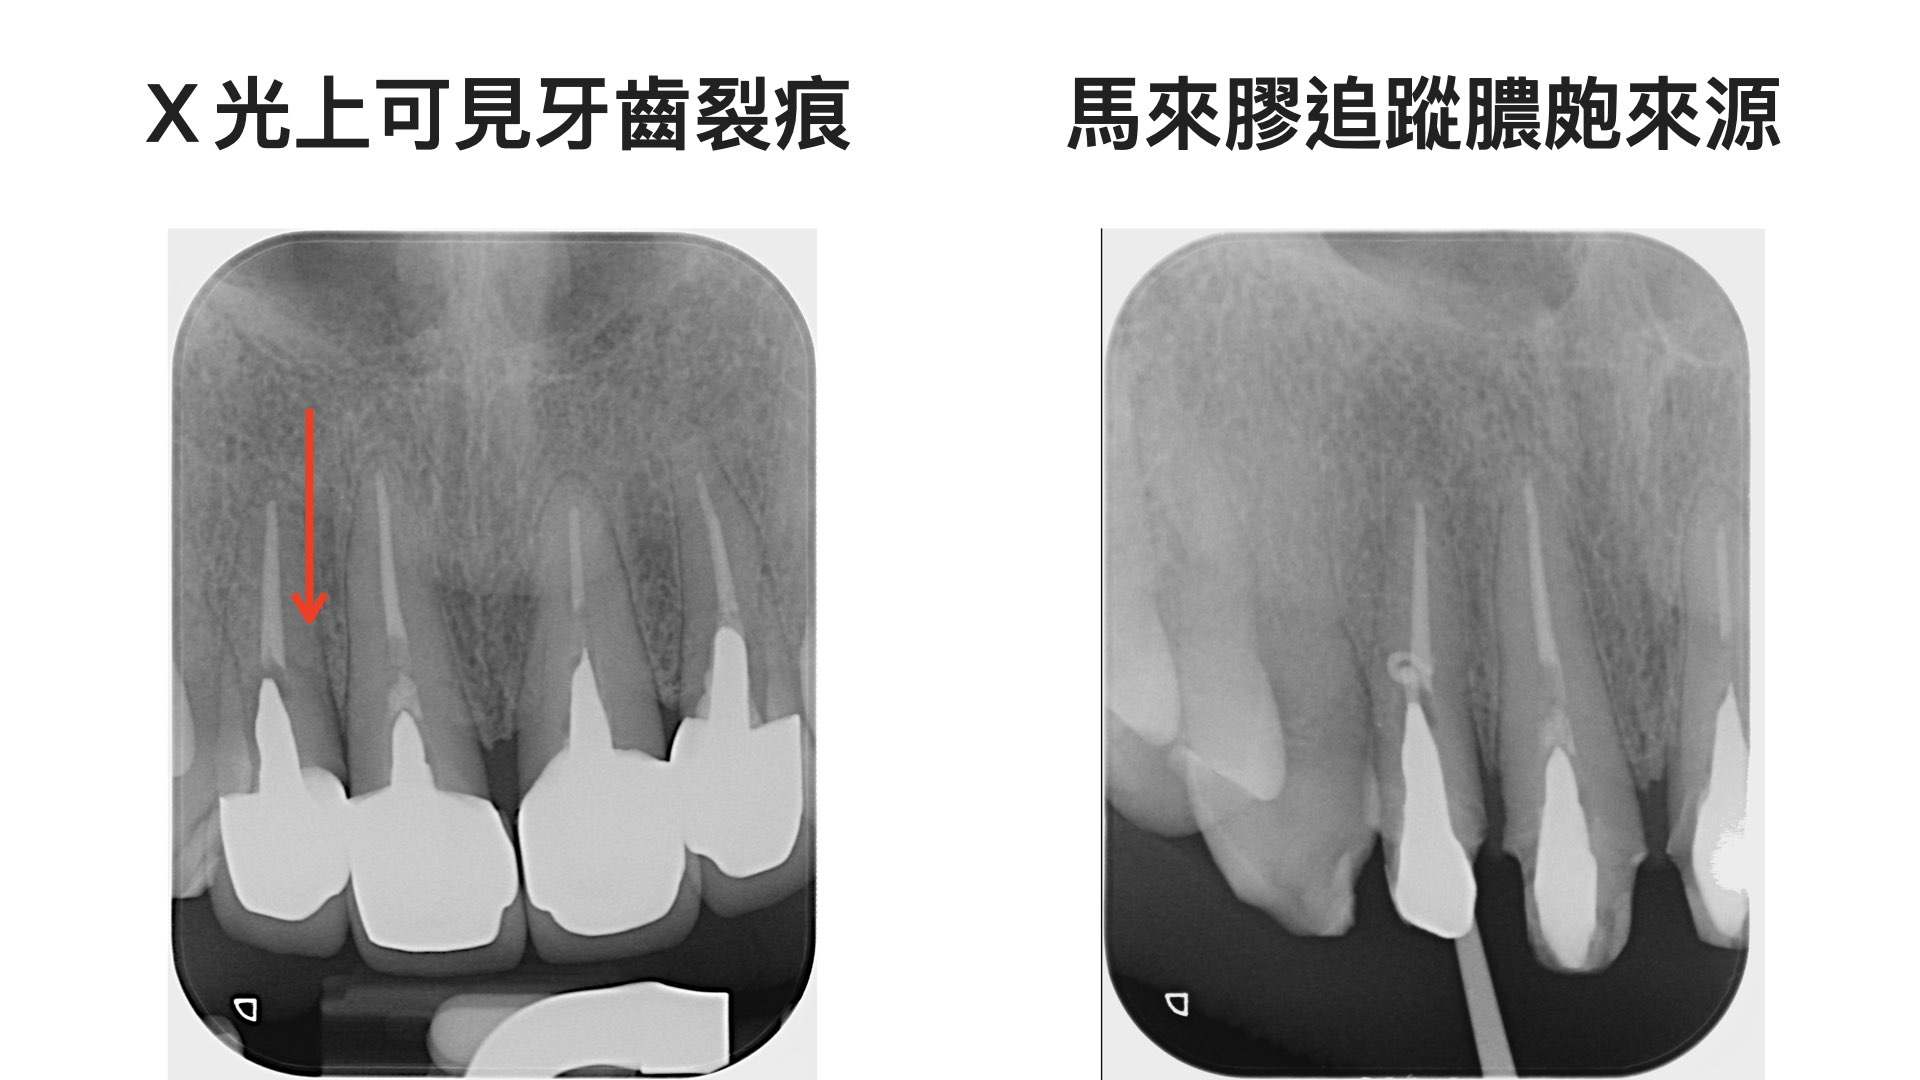

來檢查時,明顯是個裂齒症,X光檢查下,果然牙齒裂了,並且開始長膿皰了,只好計畫將牙齒移除,幸好條件不錯,同時植牙與補骨;加上他兩側犬齒因長期磨牙,造成保護性咬合喪失。

牙齒斷裂,X光檢查可發現斷裂面